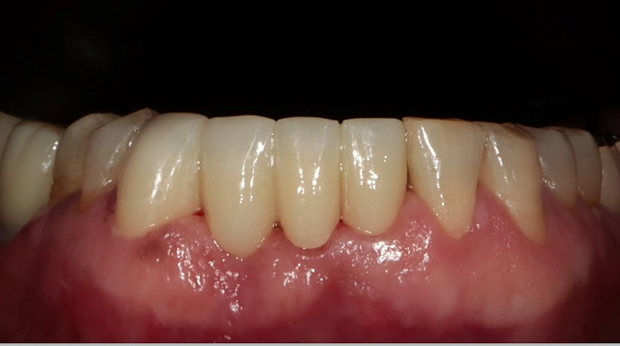

라미네이트